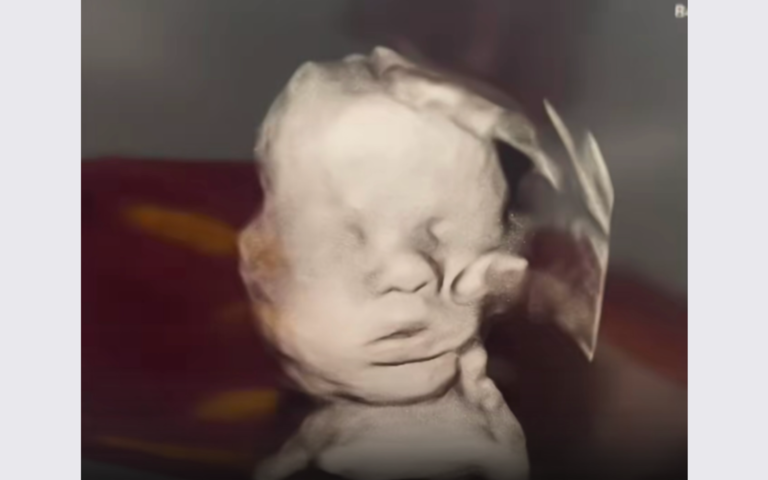

Frau entdeckt „Gottes Hand“ auf Ultraschallbild

Bewegendes Zeichen für das Leben

Eine schwangere Frau aus Cincinnati teilte einen besonderen Moment: Auf dem Ultraschallbild ihres ungeborenen Sohnes scheint sich die „Hand Gottes“ über das Baby zu legen. Diese bewegende Entdeckung wird inzwischen weltweit auf Social Media geteilt und für die Fürsorge Gottes schon vor der Geburt.